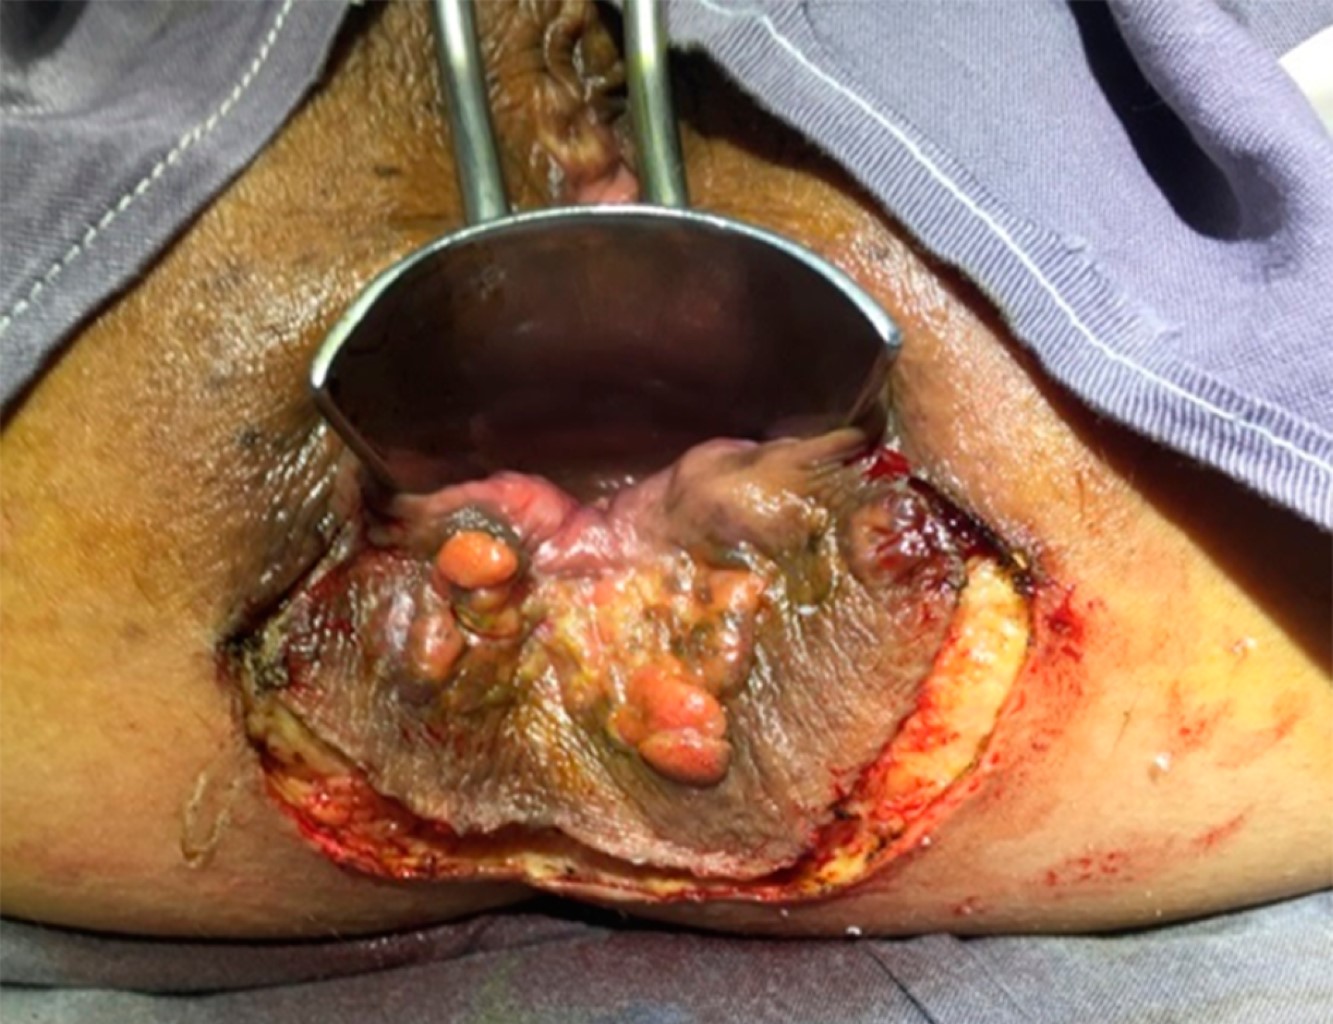

Introduction: anal intraepithelial neoplasia (AIN) is a premalignant condition of the anal region, precursor of anal cancer. Develops due to infection with oncogenic strains of human papillomavirus (HPV), its treatment and management will depend on the size of the lesion, location, histology and practice of the colorectal team. Objective: to present our experience in large high-grade AIN. Design: Presentation of two patients and review or current evidence. Material and methods: case 1: 59 year-old woman with prior know genital HPV infection, presents a lesion in the posterior anal margin, scaly with whitish areas, and uneven surface, about 5 cm in diameter with itching; case 2: 38 year-old woman with prior know genital HPV infection, present a lesion of approximately 3 cm in diameter at the posterior anal region, raised, uneven-edged, with itching. Incisional biopsy is taken and reports high grade anal intraepitheliall neoplasia. Results: it is decided to perform surgical resection in both cases. The patients did not present postoperative complications or alterations in fecal continence. The pathological report of the specimen revealed "high grade anal intraepithelial neoplasia, no evidence of invasive carcinoma and free resection margins". Conclusion: these lesions have a low rate of progression to squamous carcinoma. Local and surgical treatment versus clinical follow up has not shown important differences since it has high recurrence rates despite the treatment. However in cases of high grade AIN with symptoms, local resection can be considered.

Figure 1

Figure 2

Figure 3

Figure 4

Figure 5

Figure 6

Figure 7

Figure 8

Figure 9

Figure 10